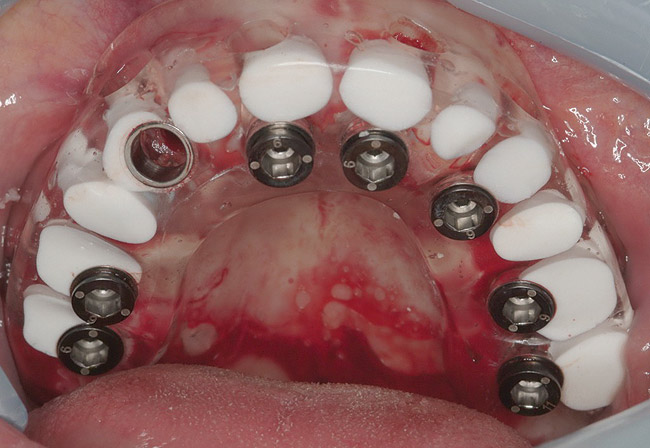

The patient was scanned with a cone beam CT scan while wearing a radiopaque scanning appliance based on her new treatment denture. Horizontal bone augmentation was confirmed radiographically, and both grafted sinuses resulted in satisfactory bone quantity for implant placement. Vertical augmentation was not attempted because of the patient’s unwillingness to forego her removable prosthesis for any period of time. Therefore, shorter implants were treatment-planned, resulting in the placement of eight implants, rather than fewer—such as six—implants, to support a full-arch fixed prosthesis. Because adequate bone and keratinized mucosa were present, a flapless, computer-guided implant insertion was performed (Figure 18). After removal of the surgical guide, placement of all eight implants could be inspected (Figure 19). Post-placement periapical radiographs are shown in Figure 20 and Figure 21.

Figure 18  Flapless, computer-guided implant insertion.

Figure 18

Figure 19  Removal of surgical guide enabled inspection of implant placements.

Figure 19

Figure 20  Post-placement periapical radiographs.

Figure 20

Figure 21  Post-placement periapical radiographs.

Figure 21